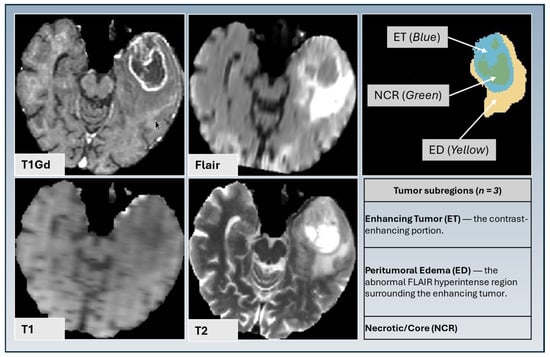

| ED | Peritumoral Edema |

| ET | Enhancing Tumor |

| NCR | Necrotic Tumor Core |